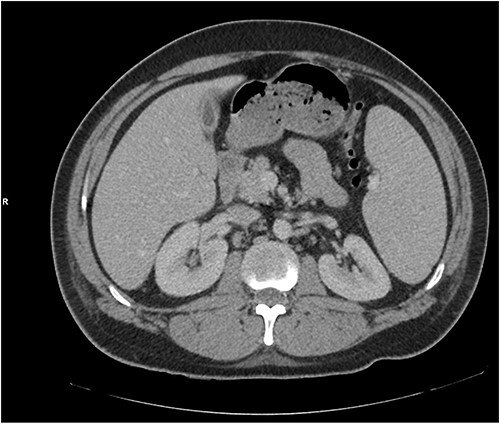

He presented with right sided abdominal pain associated with jaundice, fever, myalgia and arthralgia after receiving his second dose of the penultimate cycle of intra-renal BCG instillation. He did not have any tuberculosis contacts. His parameters on admission were stable. C-reactive protein levels were 230 mg/l and white cell count (WCC) was 6.51 × 109/l. His liver function tests were deranged, with a mixed obstructive and hepatitic picture. A CT kidneys, ureters and bladder (KUB) showed mild diffuse dilatation of the right ureter and renal pelvis with minimal amount of peri-ureteric fat stranding (Fig. 1). A CT scan of the abdomen with intravenous contrast (IV) was performed, this showed a distended right ureter down to the vesicoureteric junction, peri-ureteric fat stranding and lymphadenopathy in the aorto-caval space together with splenomegaly and atelectatic changes (Fig. 2).

A CT scan of the abdomen with IV contrast showed atelactic changes in the lung bases (top left), reactive hilar nodes (top right), a distended right ureter all the way down to the vesicoureteric junction surrounded by fat stranding (bottom left) and splenomegaly (bottom right).